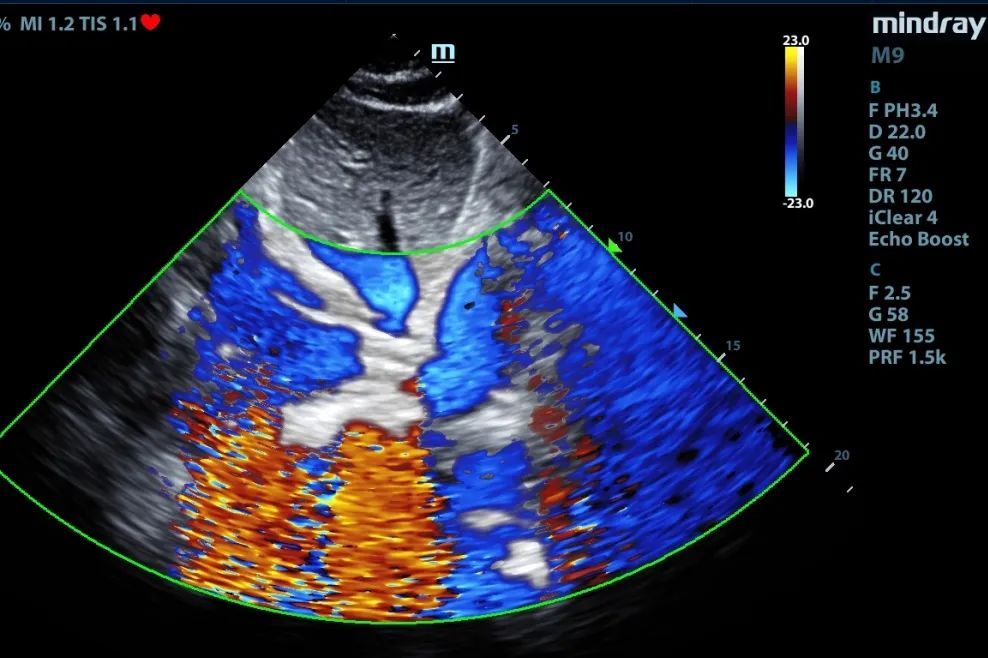

超声引导下,完成双腔颈静脉插管Crescent的置管和定位

张东山教授介绍:单管、双腔颈内插管较传统的双部位、单管插管技术难度更高;双腔插管需经颈内静脉、上腔静脉进入右心房后,再入下腔静脉,导管的三个开口需要分别位于上腔静脉、右心房、下腔静脉,且灌注口角度需要朝向三尖瓣,该要求对置管的深度及角度提出了极高要求,需要在超声引导下精准定位置管。但其优势也很明显: